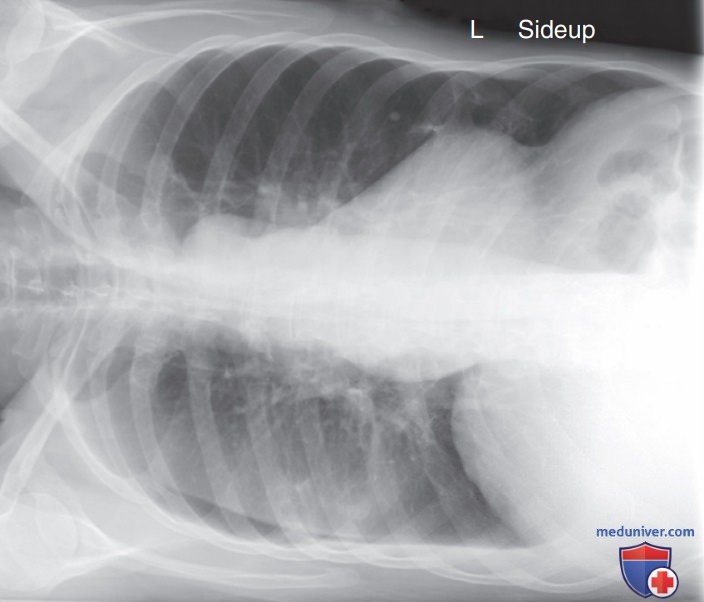

Рисунок 11 Рентгенограмма органов грудной клетки в левой боковой проекции. Правое легочное поле увеличено из-за большего РОПИ. Противоположные стороны анатомической структуры будут по-разному подвергаться проекционному увеличению, если их РОПИ существенно отличаются. Так, на этой рентгенограмме, несмотря на правильную укладку, между задними отрезками ребер справа и слева отмечается промежуток приблизительно в 1 см, хотя обе половины грудной клетки имеют одинаковый размер. Поскольку с правой стороны легочное поле и ребра характеризуются большим РОПИ, чем с левой стороны, их изображение будет казаться больше.

Рисунок A Правильное отображение и маркировка рентгенограммы органов грудной клетки в ПЗ проекции (латеро-графия на правом боку).

• Определите ту анатомическую структуру, которая подверглась большему проекционному увеличению. Чем дальше анатомическая структура находится от ПИ, тем более выражено будет проекционное увеличение (рис. A)